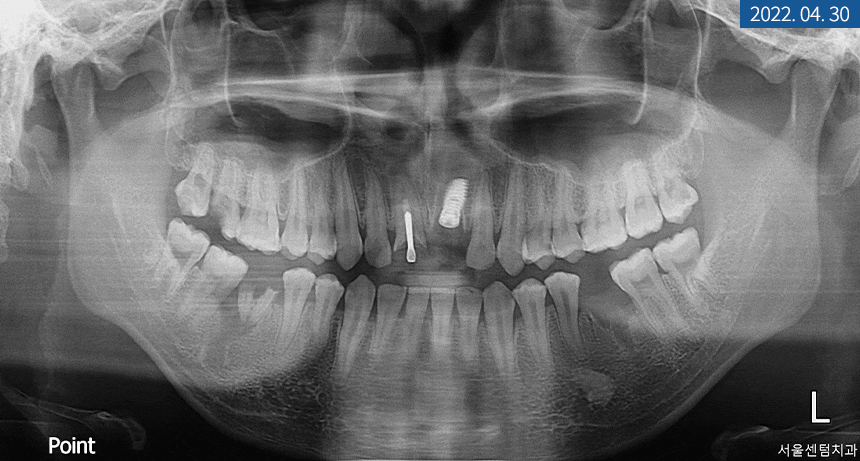

먼저 상악 #21번 어금니 발치를 진행하기로 했고

발치 후 기존 영구치 방향을 따라

인공 치근을 심은 후

필요시 GBR 골 이식재를 넣고

차폐막으로 덮기로 했습니다.

골 유착이 되는 동안에는

좌측 하악 어금니에 픽스처를 식립하고

전체 치주 질환을 개선하면서

경과를 관찰하기로 했습니다.

#21번을 진행하면서

하악 대구치도 픽스처 식립을 했는데요.

이 부분은 치조골 상태가 양호해서

바로 힐링 어버트먼트까지 체결해 드렸습니다.